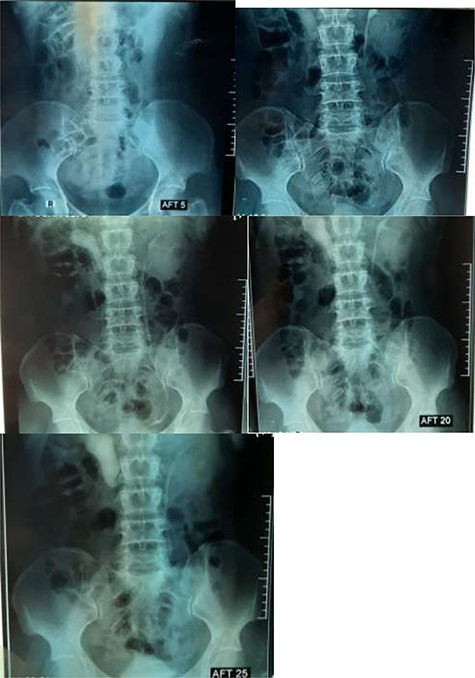

An abdominal ultrasonography revealed moderate right renal hydronephrosis and proximal hydroureter. A routine X-ray kidney-ureter-bladder (KUB) was normal. Intravenous urography (IVU) showed right renal hydronephrosis with delayed excretion and drainage (grade II) with s shape of the upper segment of the right ureter (Fig. 1). Then, the patient underwent right retrograde ureteroscopy with contrast to confirm the findings. Depending on these results, we decided to do the surgery for a right retrocaval ureter. After taking the patient consent, we had used Kocher approach to reach retroperitoneal space. After isolating of the right renal pelvis and ureter, the segment of retrocaval ureter was lower the ureteropelvic junction ~3 cm and dilated. We transected the pathological segment (~3 cm) of the ureter and then we did ureteropelvic end-to-end anastomosis. We inserted a double-j stent (Fig. 2). After a month, there was no hydronephrosis, and we removed the double-j stent. Six months follow-up demonstrates complete resolution of this pathology.

In the literature, retrocaval ureter has been classified into two clinical types, in accordance with the common radiological appearance. The more common type 1 (also named ‘low loop’) is characterized by the so-called ‘typical S’ or ‘fishhook’ deformity of the ureter to the level of the obstruction [3]. In this case, the abnormality was type 1 and the obstruction was at the right side beside the lateral margin of the IVC at the level of lumbar vertebrae L2–L3.

The imaging studies are important for an accurate preoperative diagnosis and successful surgical management. Abdominal ultrasound demonstrates hydronephrosis and proximal hydroureter without calculus. The IVU shows typical ‘fish hook’ or ‘J’- or ‘S’-shaped deformity in the proximal dilated ureter with moderate hydronephrosis. Nowadays, computed tomography urography is preferred over IVU or retrograde pyelography (RPG) as it may depict the anomaly in three dimensions giving the most ‘wholesome’ solution to its diagnosis [3]. For our patient, ultrasonography revealed moderate right renal hydronephrosis, and proximal hydroureter and the IVU showed right renal hydronephrosis with delayed excretion and drainage (grade II) with s shape of the upper segment of the right ureter, and we considered IVU result as a diagnosis.